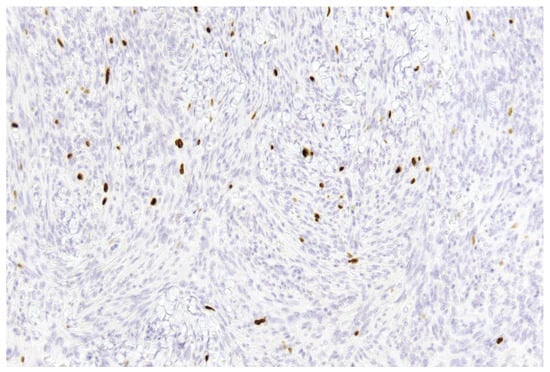

- Improved discrimination of neoplastic versus non-neoplastic cells: Unlike single-slice Ki-67 immunostaining (Figure 1), dIHC detects both markers on the same section, allowing precise differentiation between proliferating meningothelial tumour cells and components of the non-neoplastic microenvironment. EMA highlights the cytoplasm of meningothelial cells in brown, while Ki-67 marks proliferating nuclei in red. Only double-positive (EMA+/Ki-67+) cells are included in the PI count (Figure 2), whereas Ki-67-positive but EMA-negative elements (e.g., macrophages, lymphocytes, endothelial cells) are excluded (Figure 3).

Figure 1. Example of a single-slice Ki-67 staining in a grade 1 meningioma (case 1). Brown-stained nuclei indicate cells in the proliferative phase (10× magnification).